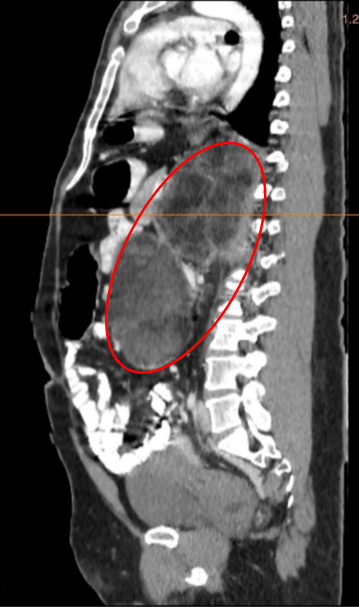

Adrenal CT scan showed heterogeneously enhancing masses with diffuse areas of fat densities and myeloid components seen in the bilateral adrenal glands measuring 21.9 x 12.4 x 12.3 cm (CCxWxAP) on the left and 11.1 x 7.2 x 6.9 cm (CCxWxAP) on the right with mean Hounsfield units (HU) -31 in the left and HU -18 in the right (see Figure 1).

Figure 1. A axial view, B. sagittal view. Abdominal CT images of the patient showing heterogeneously enhancing masses with diffuse areas of fat densities and myeloid components seen in the bilateral adrenal glands (red circle) measuring 21.9 x 12.4 x 12.3 cm (CCxWxAP) on the left and 11.1 x 7.2 x 6.9 cm on the right. HU values as follows: Left  adrenal: Mean: -31 HU, Min: -114 HU, Max: 60 HU, Right adrenal: Mean: -18 HU, Min: -87 HU, Max: 41 HU.